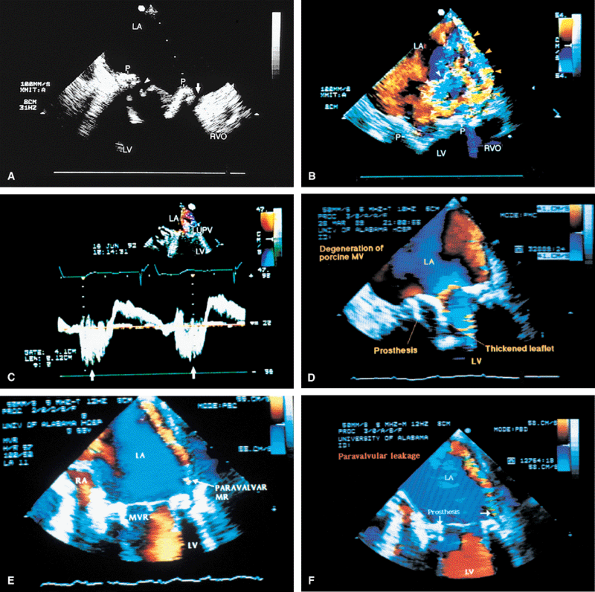

FIGURE 5.37. A–H. Porcine aortic prosthesis: normal. The leaflets (A, arrowheads in C–E and G, arrow in F) and the stents (ST, arrows in E and G) of the prosthesis (P) are well seen. Because the metallic stents are highly echogenic, they may obscure the thin leaflets. It may be necessary to use multiple transducer angulations to see the leaflets as completely as possible. F. M-mode tracing of the prosthesis (AP) shows it in the open and closed position (arrows). H. Gross specimen of a normal porcine prosthesis in the aortic position. AO, aorta; LA, left atrium; LV, left ventricle; RV, right ventricle; RVO, right ventricular outflow tract. |

FIGURE 5.38. Porcine aortic prosthesis: degeneration/prolapse/valvular regurgitation. A. A thickened, stenotic prosthesis (P) with marked restriction of the opening (arrowhead) in systole. B–E. Another patient with thickened prosthetic leaflets (arrows in B,C) prolapsing into the left ventricular outflow tract (LVOT). D. The proximal portion of the aortic regurgitation (AR) jet (arrows) is not imaged because of acoustic shadowing produced by the calcified prosthesis. E. Severe AR (arrow) is seen in this patient. F.Another patient with very mild thickening and degeneration of the porcine prosthesis (PAV). G. More severe thickening and degeneration of the prosthesis (P) than that seen inF. H,I. Another patient with a degenerated PAV. The arrow in H points to a linear echo protruding from the prosthesis in diastole. This finding is common in the setting of degeneration. J–L. A different patient with a heavily calcified prosthesis (P) that prolapses into the LVOT (arrows). Associated severe AR is shown in L. M,N. Linear echoes (arrows) that prolapse into the LVOT in a patient with a thickened, degenerated heterograft prosthesis (P). O. Prolapse (arrowhead) of a heterograft prosthesis (P) in a patient who has an aortic (AO) aneurysm. P. Mild thickening and degeneration of a heterograft prosthesis (P) in another patient with aortic root aneurysm and dissection. F, dissection flap; FL, false lumen. Q,R. Gross specimens with calcification and thickening on the ventricular (Q) and aortic (R) aspects of a heterograft prosthesis. LA, left atrium; LV, left ventricle; MV, mitral valve; PA, pulmonary artery; RA, right atrium; RV, right ventricle; RVO, right ventricular outflow tract. |

FIGURE 5.39. Porcine aortic prosthesis: valvular and paravalvular regurgitation. A. Prolapse (arrowhead) of a thickened and degenerated prosthesis (P). B–D. Aortic regurgitation (AR) flow signals are shown moving into the left ventricular outflow tract (LVOT) posteriorly from beyond the confines of the prosthesis, indicative of a paravalvular leak. C. Associated valvular regurgitation originating from within the confines of the aortic prosthesis. An anterior paraprosthetic leak is also demonstrated (white arrow). The black arrows in B and C show the site of the posterior paravalvular leak. E. Another patient with heterograft prosthesis (P) cusp prolapse demonstrating severe AR.LA, left atrium; LV, left ventricle; PA, pulmonary artery; RA, right atrium, RV, right ventricle; RVO, right ventricular outflow tract. |

FIGURE 5.40. Porcine aortic prosthesis: cusp rupture. The arrowheads in A and B show a ruptured cusp prolapsing into the left ventricular outflow tract (LVOT), with severe aortic regurgitation (AR) shown in C through E (arrowheads in D, arrows in E). Diastolic mitral regurgitation (MR) (arrowheads) from severe AR is noted in C. F is a gross specimen of a thickened and calcified porcine aortic valve with cusp rupture (circled). AO, aorta; LA, left atrium; LV, left ventricle; P, prosthesis; RA, right atrium; RV, right ventricle. |